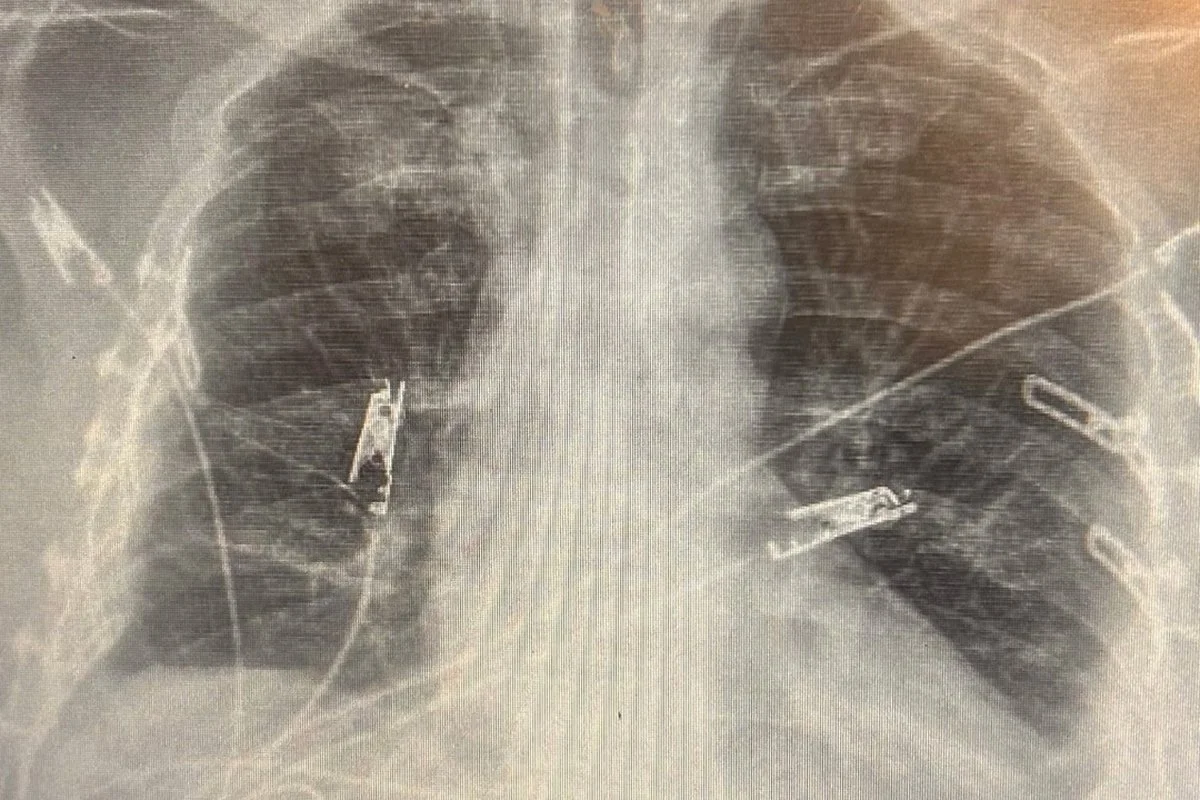

Tony broke every rib except two.

His lungs were severely damaged.

While hospitalized, doctors drained more than 4,000cc of blood from his chest. He required six blood transfusions, multiple surgeries to plate his ribs, and procedures to help his lungs function again without oxygen support.